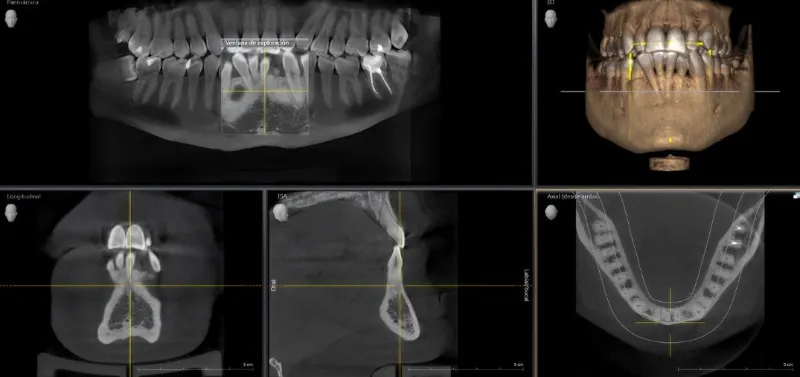

Tomografia komputerowa (CBCT)

Trójwymiarowa diagnostyka struktur zębów i kości szczęk, umożliwiająca precyzyjne planowanie leczenia.